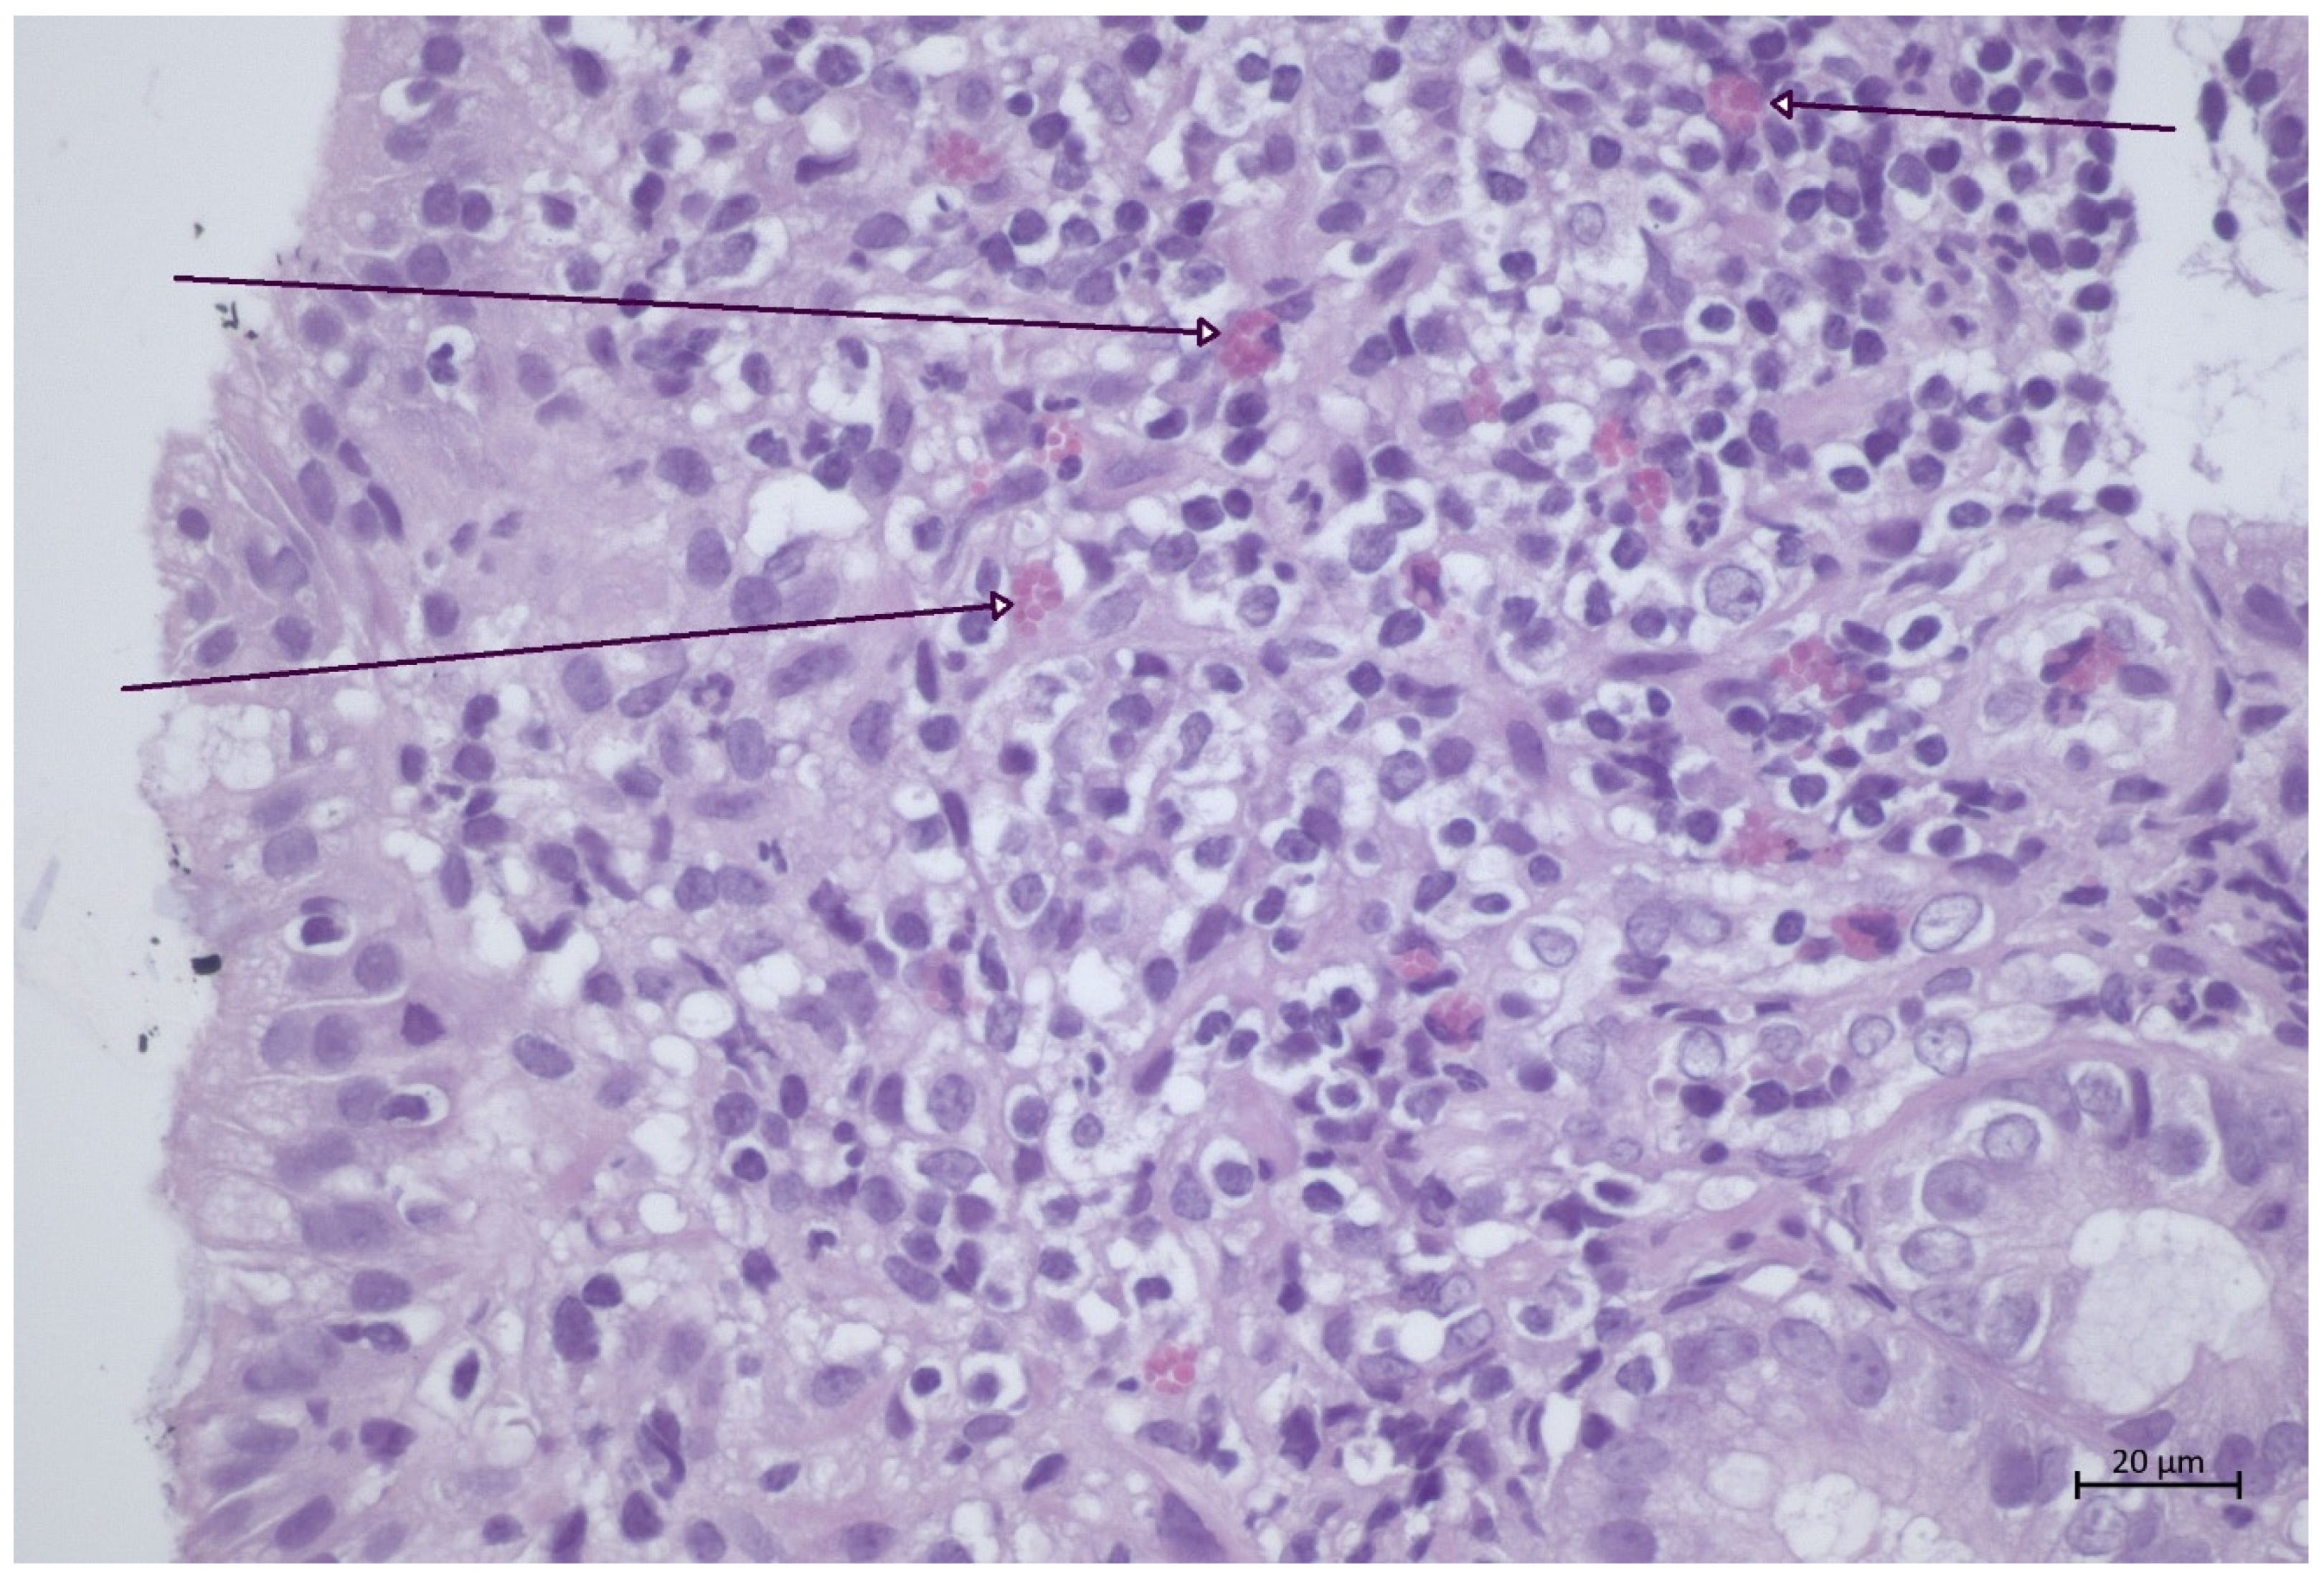

3.1. Duodenal Mucosal Samples

3.1.1. Superficial Epithelium

3.1.2. Lamina Propria

3.1.3. Submucosa

3.2.2. Lamina Propria

3.2.3. Submucosa